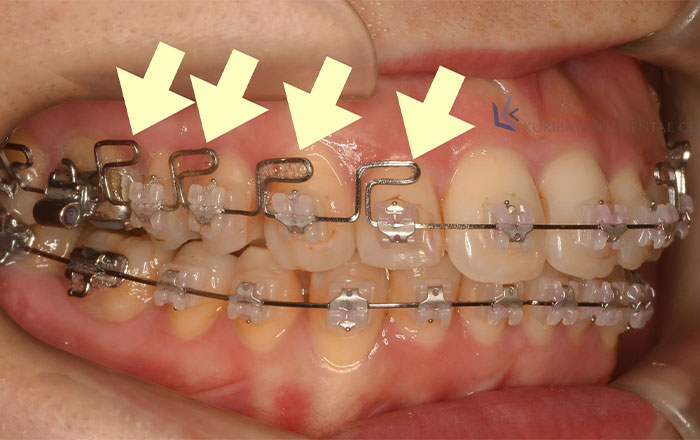

1.MEAW

MEAWは、マルチループとも呼ばれ、従来のストレートワイヤーとは異なり、複雑な歯の形に曲げることで、歯を前後・上下に3次元的に移動できるようにした装置です。

MEAWがあることで、顎の骨や歯を動かすため、歯を抜かずに治療ができたり、歯の根っこの方向を整えやすく、また、噛み合わせのバランスも整えやすいというメリットがあります。

MEAWにより、歯並び・傾き・ねじれを矯正することができます。

また、MEAWはストレートワイヤーを患者さまに合うように歯科医師が1つ1つ手作業で曲げています。

複雑な形の分、ストレートワイヤーよりも歯みがきが難しくなるため、いつも以上にむし歯・歯周病予防が大切です。